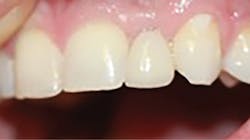

After a three-month integration period, final impressions were taken for a screw-retained crown. The procedure was noneventful, and not only was the patient happy having a provisional tooth, but the relief offered with a permanent fixed solution changed his entire outlook (figures 5 and 6).

Figure 6: Final implant restoration

A 1.8 mm x 14 mm Anew implant (Dentatus) was selected, and a surgical guide was fabricated for a flapless approach. In this instance, a healing cap was placed, and the existing flipper was relieved to address financial concerns (figures 9 and 10). A screw-retained crown was fabricated three months post insertion (figures 11 and 12). The patient reported no postoperative discomfort, and the case remains successful, as shown in the two-year postoperative x-ray (figure 13).

Figure 12: Final crown seating